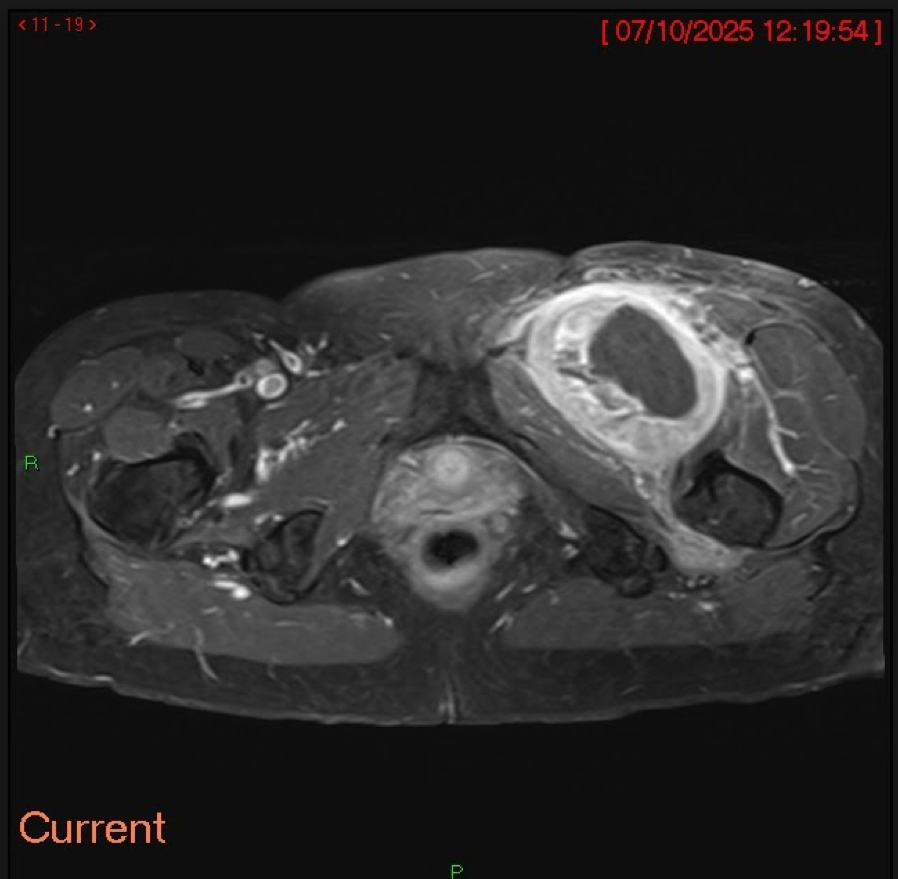

Fig.06. MRI Pelvis with T2-weighted PD fat-suppressed sequences again shows a large, heterogenous intermuscular mass in the medial compartment of the left upper thigh with associated mass effect and perilesional oedema.